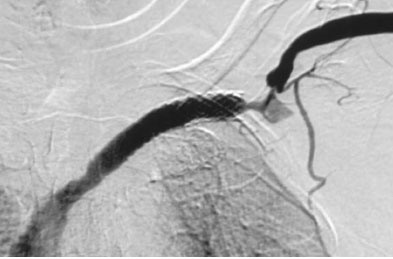

![]() 病人最终选择了10mm直径,9cm长的Viatorr覆膜支撑架,其中覆膜部分为7cm,2cm为裸支撑架。释放杆为10F,41厘米长。支撑架前端裸支撑架部分进入上腔静脉,覆膜部分在狭窄段锁骨下静脉。释放支撑架后,用扩张球囊扩张到10mm。最后影像如上图所示。3个月后血管造影发现,在支撑架远心端的支撑架未覆盖的血管有轻度狭窄。未做处理。

![]() 上图为术后11个月血管造影复查。后进行PTA(未显示)。